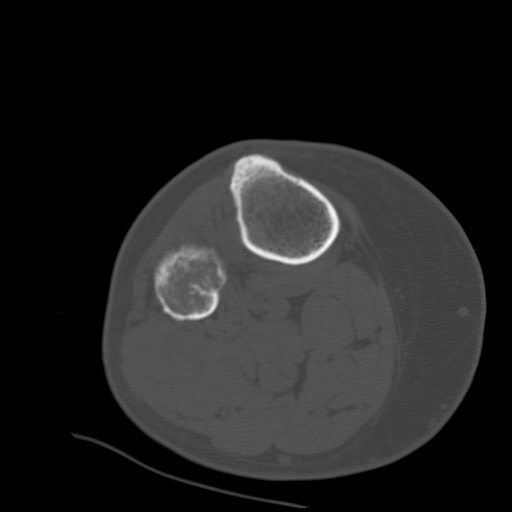

CT:

Note the distruction of the cortex. |

- In this particular case there is

extension of the osteolytic lesion (arrow)

towards the diaphysis highly

suggestive of aggressive behavior. On the CT scan, the cortex

overlying the tumor is thickened and blurred which reflects

permeation of haversian and Volkmann's canals with subequent bone

apposition over a long period of time. This is a common feature of a

low-grade chondrosarcoma.